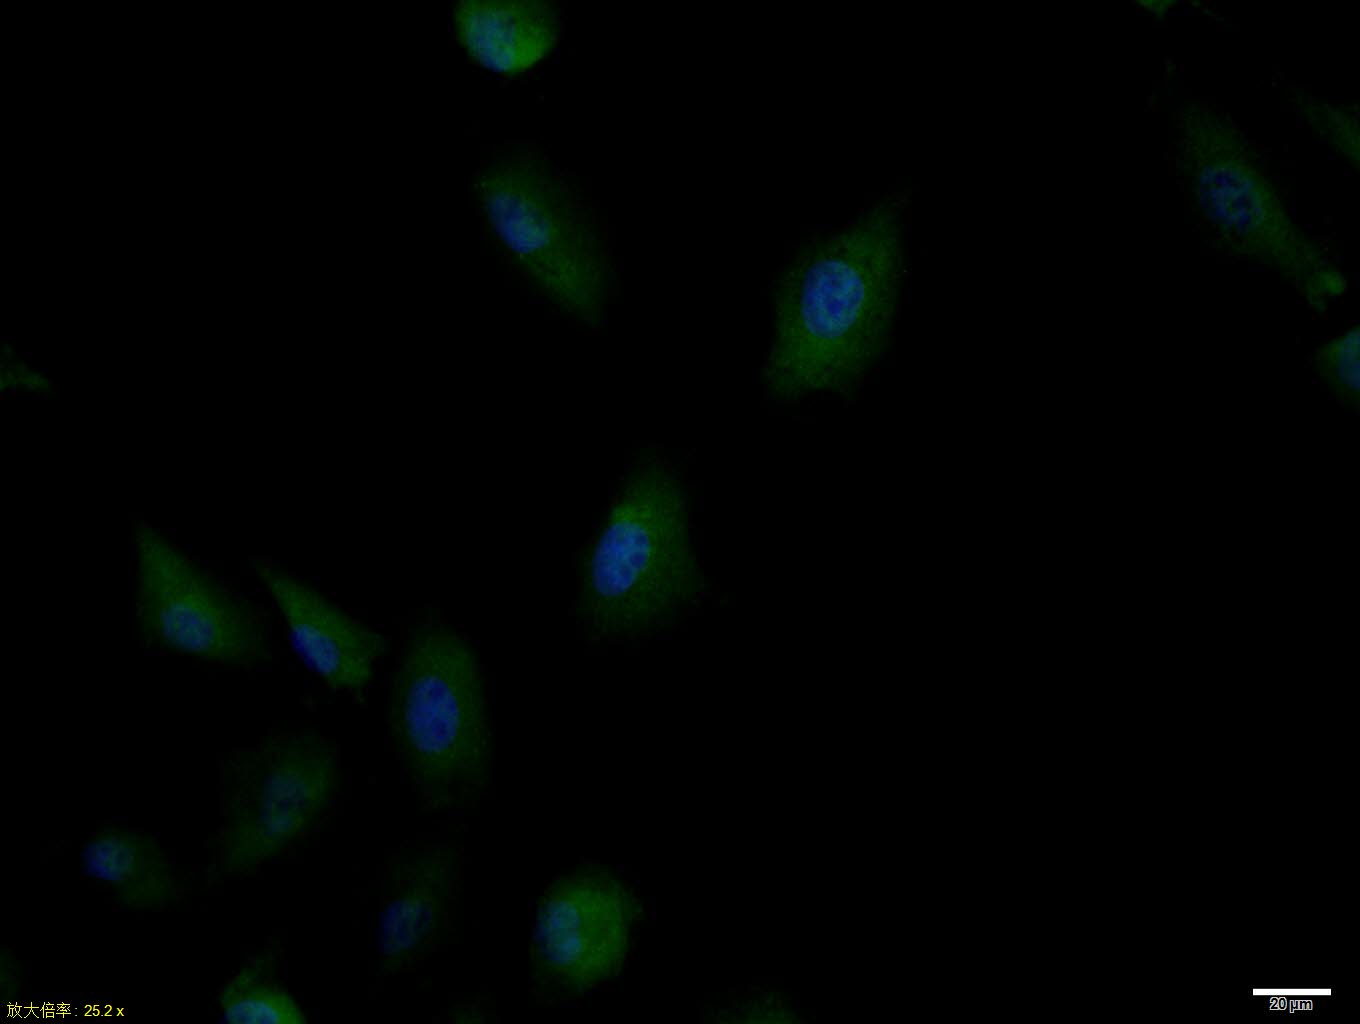

phospho-IRS1 (Ser636 + Ser639) Polyclonal Antibody

• IF

• ICC/IF

Applications IHC-P, IHC-F, IF, Flow-Cyt, ICC/IF

Subcellular location Cell membrane